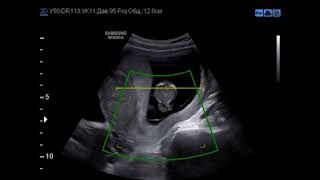

Случай правосторонней диафрагмальной грыжи

Диафрагмальная грыжа

Диафрагмальная грыжа – аномалия развития, характеризующийся наличием врожденного дефект диафрагмы, через который, во внутриутробном ...